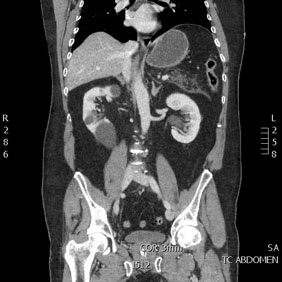

< Volver a "Tomografía Computarizada (TC) con Inteligencia artificial"Se utiliza para el estudio de los diferentes órganos de abdomen y pelvis (hígado, riñones, intestino, próstata, ovarios…).

Si no hay ninguna contraindicación, es muy probable que le inyectemos por vena un contraste yodado, que nos aportará una mejor caracterización de los órganos y visualización de las diferentes patologías.